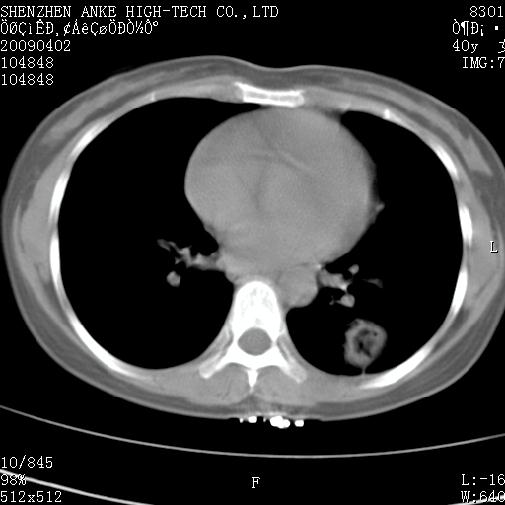

以下是引用随光逐影在2009-4-2 12:16:00的发言:[br]考虑左肺下叶背段继发性肺结核,结核球形成;建议追踪复查。

以下是引用gudu医生在2009-4-2 11:27:00的发言:[br]周围型肺癌

以下是引用卜一在2009-4-2 13:31:00的发言:[br][br] [br] 空洞壁厚不均 胸膜凹陷征。周围型肺癌可能 不排除干酪坏死型肺结核及坏死性肉芽肿。 [br] [br]支持!

以下是引用ct诊断高手在2009-4-2 13:04:00的发言:[br]空洞壁厚不均 胸膜凹陷征。周围型肺癌可能 不排除干酪坏死型肺结核及坏死性肉芽肿。